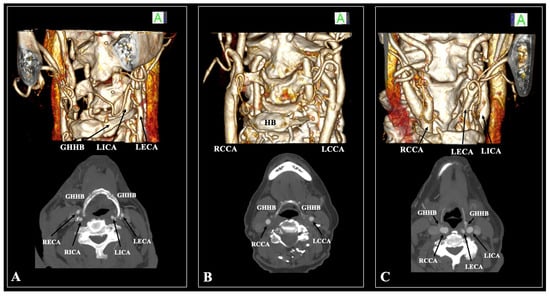

- In cases of suprahyoid CB, the minimum distance GH-CCA was measured (Figure 3)

- In cases of infrahyoid CB, the minimum distances GH-ICA and GH-ECA were measured (Figure 3)